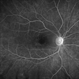

- toxic maculopathy

Clarus 700 - Description

- A 50-year-old woman with a 15 year history of pentosan polysulfate treatment for interstitial cystitis.